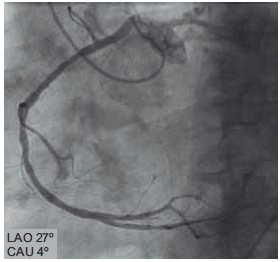

Ao realizar cineangiocoronariografia de mulher com 45 anos, tabagista, com queixa de dor torácica, observa-se o seguinte achado.

Trata-se de origem anômala